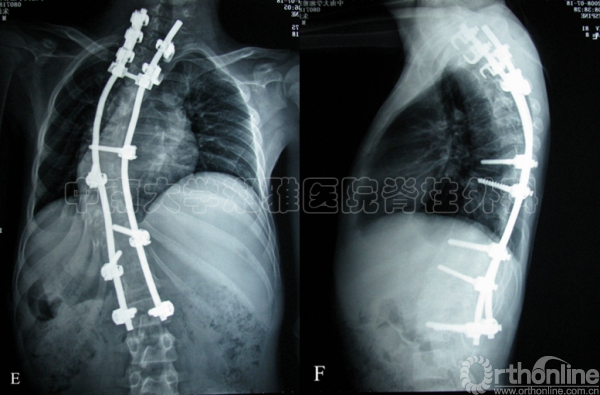

A-B:一期行后颅窝减压,蛛网膜粘连松解术,二期行后路钉棒矫形内固定植骨融合术后1年上端椎脱钩,出现PJK46°。

C-D:翻修术中相

E-F:予以后路翻修术,延长了固定节段,PJK改善明显。